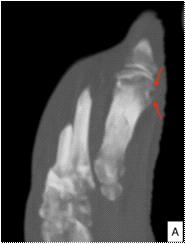

Majority of the patients had abnormal appearances of the HP region on MRI (Table 5) (Figs 1&2). Empty sella with varying thickness of the remaining pituitary tissue was the commonest abnormality noted (28 patients, 52.8% of the cohort). Only 3 patients (5.66%) had apparently normal looking HP region. Hypophysitis was diagnosed retrospectively in 1 lady with ES, whose previous MRI was consistent with hypophysitis11. One male with hypophysitis

Viper bite (n=16) Partial empty sella: 14; hypoplastic pituitary: 1; normal HP region: 1

Sheehan’s syndrome (n=13) Partial empty sella: 12; hypoplastic pituitary: 1